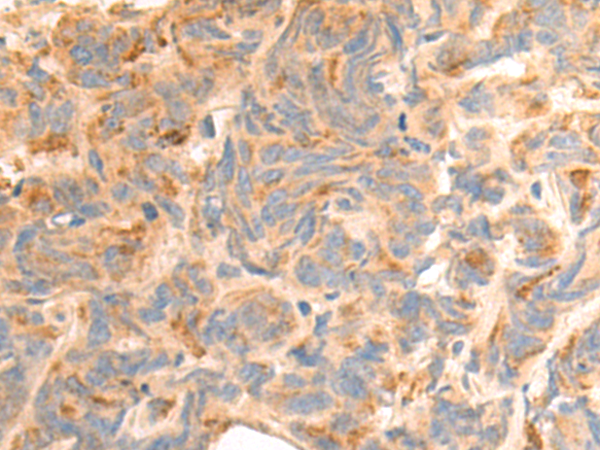

分类: 科研抗体货号: P07409别名: ARM1; EMSP; PSTS; AI2A1; EMSP1; KLK-L1; PRSS17; kallikrein应用: IHC反应种属: Human